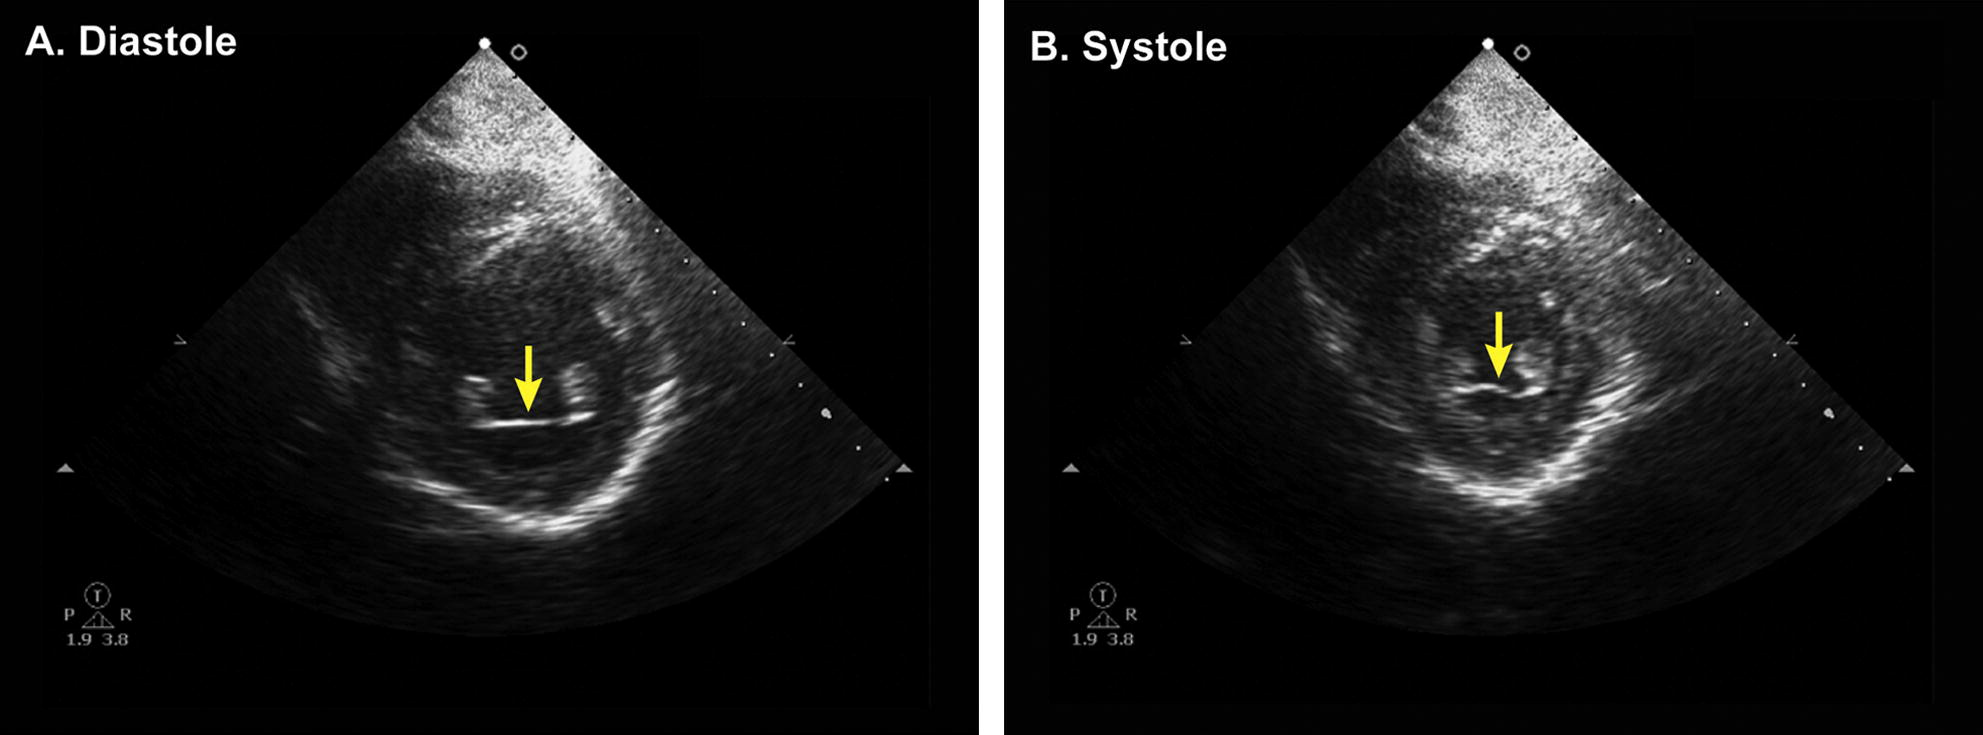

LV Thrombus

Features:

• regional wall motion abnormality

• apical location

• distinct margin with jagged edges

• movement separate from the underlying endocardium

• higher echo density as compared with the myocardium

Mimic